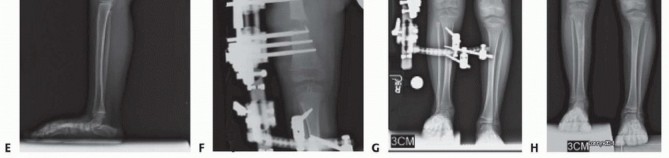

Lengthening

The number of lengthenings that are required for type 1 CFD is determined by the initial LLD prediction. Patients that do not require any preparatory surgery can undergo their first lengthening as early as age 2 years and preferably before age 4 years. Patients that do require preparatory surgery (eg, superhip, Dega) can undergo their first lengthening 1 year or more after the preparatory surgery. This is usually between ages 3 and 4 years. Between 5 and 8 cm can be obtained during each lengthening.

For type 1 CFD, the femur should be lengthened by using a distal femoral osteotomy instead of a proximal femoral osteotomy.

Distal osteotomies allow for better regenerate bone formation because they have a broader cross-sectional diameter and because the bone is not sclerotic or dysvascular, which often is the case in the proximal femur of patients with CFD. Distal osteotomies can also be used to simultaneously correct the valgus deformity of the distal femur.

releases that were addressed during a previous superhip or superknee procedure do not need to be repeated. Illustration 13 for Treatment for Congenital Femoral Deficiency: What You Need to Know Illustration 14 for Treatment for Congenital Femoral Deficiency: What You Need to Know Illustration 15 for Treatment for Congenital Femoral Deficiency: What You Need to Know FIG 7 • A. Patient with Paley type 3b CFD with severe leg length difference and knee flexion contracture. B. Clinical photo just prior to rotationplasty. C. Radiograph after Paley modified Brown rotationplasty. D. Photograph showing the appearance after rotationplasty. E,F. Side views showing knee flexed (ankle at neutral) and knee extended (ankle plantar flexed). _ Lengthening via External Fixators *_ Femoral lengthening with an external fixator can be performed with various devices. The essential principle of lengthening with external fixation is to stabilize the knee during lengthening while allowing for knee motion. This is accomplished by using hinges and external fixation of the tibia. From 1987 to 2000, the author used only the Ilizarov apparatus with fixation across the knee joint with a hinge for all CFD lengthening cases. This method has previously been described.9 A monolateral external fixator was not used because it could not articulate across the knee joint. From 2000 to 2009, the author modified the Orthofix Limb Reconstruction System (LRS) rail (Orthofix, Inc., McKinney, TX) with the Sheffield Ring Fixation System arch (Orthofix) to articulate across the knee with fixation to the tibia. This method was used for all CFD cases between January 2000 and May 2009. From 2009 to the present, the author designed a special external fixator specifically for articulated spanning of the hip and knee joints. The Modular Rail System (Smith & Nephew, Memphis, TN) has been used in all CFD cases since June 1, 2009.

Because of the correction of the abduction contracture and the opening wedge of the Dega, it is not possible to close the apophysis. The apophysis is pulled up and the level marked with a pen. The crest is then resected using a saw until the medial and lateral apophysis can be repaired without excessive tension ( TECH FIG 3C,D ). This is called the abductor slide technique . The TFL is then sutured to the rectus femoris ( TECH FIG 3E ). The incision is closed in layers. A suction drain is used and is left in place until the drainage stops (<10 mL per 24 hours), which can take several days. Prophylactic antibiotics are administered intravenously until the drain is removed. Illustration 30 for Treatment for Congenital Femoral Deficiency: What You Need to Know Illustration 31 for Treatment for Congenital Femoral Deficiency: What You Need to Know Illustration 32 for Treatment for Congenital Femoral Deficiency: What You Need to Know TECH FIG 4 • A,B. CFD Paley type 1b with delayed ossification of femoral neck. C. Superhip procedure at age 2 years including insertion of BMP in femoral neck. D. The neck is fully ossified by age 3 years. E,F. First lengthening is performed at age 4 years with Smith & Nephew Modular Rail System external fixator with articulation across the knee joint. G. Eight centimeters of lengthening is achieved. H. Removal of external fixator with Rush rodding of bone to prevent fracture. A spica cast is applied with the hip in full extension, neutral abduction, and neutral rotation. The knee is splinted in full extension. The cast is bivalve to allow for swelling. One week after surgery, the cast is made removable and gentle flexion and extension ROM of the hip and knee started. TECH FIGS 4 and 5 are two case examples of superhip procedures. *

Illustration 33 for Treatment for Congenital Femoral Deficiency: What You Need to Know Illustration 34 for Treatment for Congenital Femoral Deficiency: What You Need to Know TECH FIG 5 • A. Two-year-old girl with CFD Paley type 1b with delayed ossification and severe angulation of the subtrochanteric level of the femur. B. The deformity is fully corrected, and the femur is healed after the superhip surgery. C. Lengthening of the femur was performed at age 4 years. D,E. X-rays after lengthening of the femur 7 cm and insertion of Rush rod. 1. # Superknee Procedure